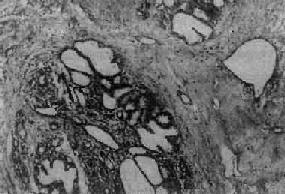

纤维腺病

图13-24 纤维腺病

末梢导管、腺泡和间质均呈明显增生,部分腺泡及导管扩张,间质内有一些淋巴细胞浸润